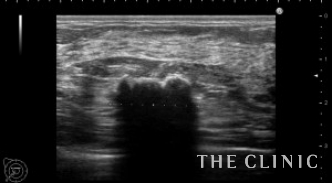

触診では両側乳房にしこりを触れ、エコーでは2cmを超える石灰化したしこりを認めました。何度か注射針で吸引しているのでしこりは辺縁不整で周囲組織と癒着している状態です。